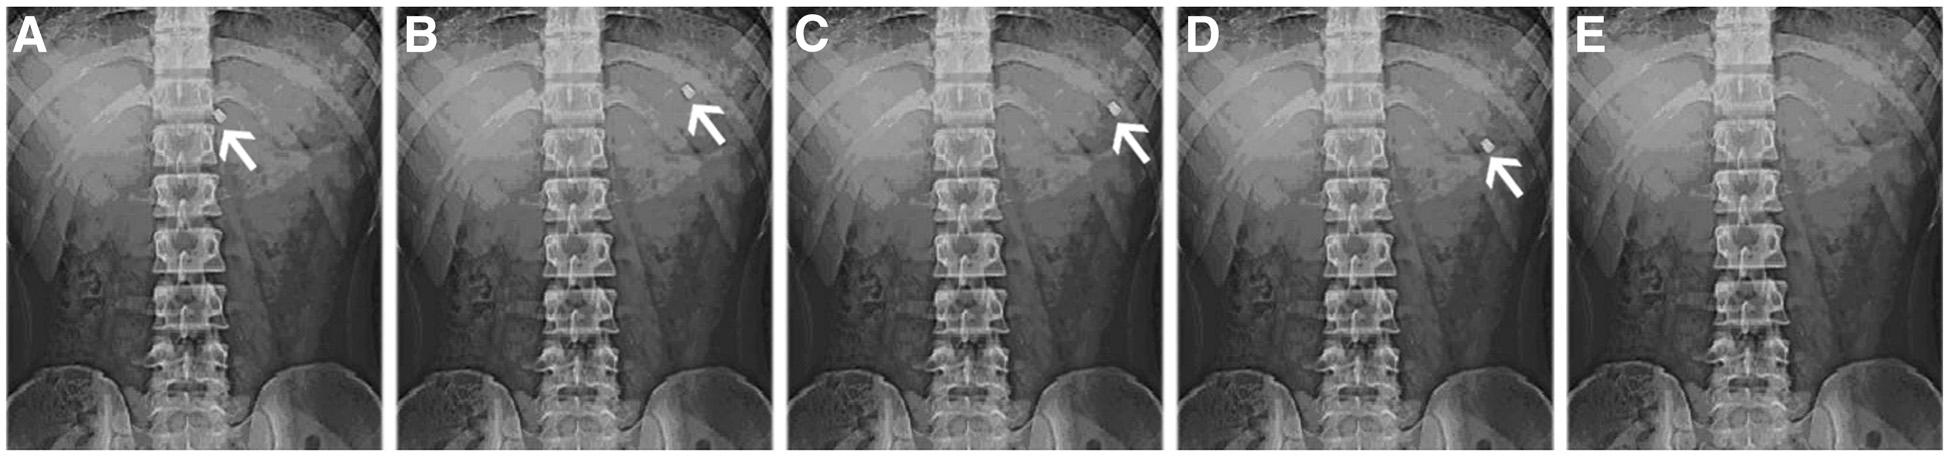

In the fed state after the high calorie high fat breakfast, the BGRFT was observed to be buoyant on the gastric contents up to 6 h after administration as shown in fig. 11 (a) at 0.5 h, fig. 11 (b) at 2 h, fig. 11 (c) at 4 h, fig. 11 (d) at 6 h and disappeared at 8 h shown in fig. 11 (e). Hence, in the fed condition, the floating system showed a 5 to 6 h of prolonged GRT over the fasted state. The evaluation of the BGRFT of ranitidine HCl and clarithromycin intragastric behaviour in humans, showed the actual floatability of the tablet on the gastric content. This study has demonstrated that in the fasted state under the influence of strong motor activity, there was no enhancement of GRT of gastro retentive floating tablet, whereas there was a prolonged GRT of approximately 6 h in a fed state.

Fig. 11: X-ray photographs of gastric floating tablets of bilayer gastric retentive floating tablets containing ranitidine HCl and clarithromycin under fed state after (a) 0.5 h (b) 2 h (c) 4 h (d) 6 h and (e) 8 h